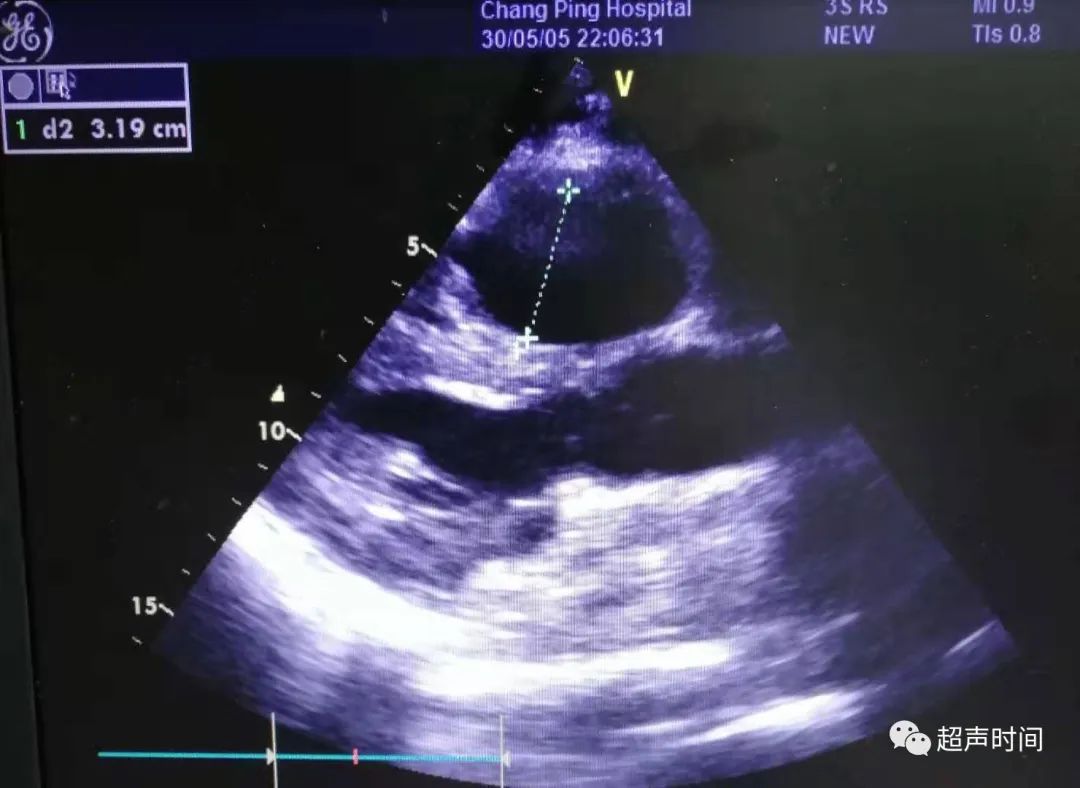

急诊床旁心脏超声所见如下:

图 1 和图 2 左室长轴切面示右室显著增大,其前壁运动减弱、消失,室间隔呈矛盾运动,左室收缩功能正常